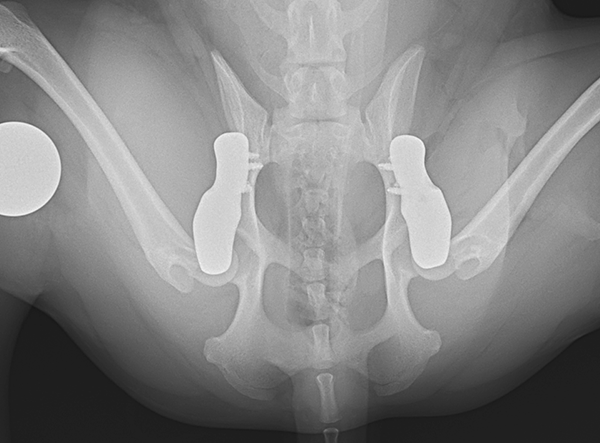

The surgery involved implanting a 2.4 mm 3D HIP Patient-Specific Implant (Titanium) to address severe bilateral hip dysplasia. According to Prof. Dr. Björn Meij (Utrecht University), this miniature Shiba Inu represents the smallest patient on Earth to have successfully undergone this advanced orthopedic procedure. The precision and adaptability of the 3D HIP system allowed for a stable and minimally invasive intervention, tailored to the patient’s unique anatomy.

- Bilateral Option: Enables treatment of both hips in a single surgery.

This landmark case demonstrates the versatility of 3D HIP and its ability to push boundaries in small-animal orthopedics. By successfully treating such a small and delicate patient, this procedure sets a new standard for precision surgical solutions in veterinary medicine.